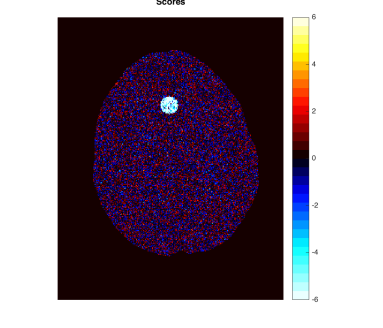

As a motivating example that will be detailed in Section 5, Figure 1 shows data from the phantom experiment in Qin et al., (2017) simulating pre- and post-treatment scans with a tumor lesion. A direct voxelwise difference between the two scans shows a global non-homogeneous background change while failing to detect changes in the lesion (Figure 1, Row 1 and Column 3). This observation suggests that background adjustment is necessary in voxelwise comparisons to reduce confounding by tissue-dependent changes not related to the disease, in order to isolate localized differences that are relevant to assess the disease status.

In the first half of this paper, we study the standardization of a Gaussian mixture model systematically in various but simple ways. We show that, surprisingly, the tail distribution of the standardized scores is favorably close to standard normal in a wide range of scenarios while being conservative at the tails, making it suitable for statistical inference. Compared to the standardization method for background adjustment in Guo et al., (2014) and Qin et al., (2017), we consider several variations using both soft and hard assignment of the observations to latent classes. In the data application in Figure 1, the analysis based on the model-based standardized differences proposed in this paper is successful (Row 2 and Column 3) as the background difference is now randomly distributed around zero and the lesion change is clearly visible; see Section 5 for more details. The distributions of the corresponding standardized scores are evaluated here theoretically, numerically and via simulations. Theoretically, it is shown that the standardized scores are indeed close to standard normal under a variety of extreme parameter settings. In non-extreme parameter settings, it is shown numerically that the soft assignment methods lead to conservative tail probabilities, making them valid for hypothesis testing purposes. It is also shown that the tail probabilities are not very sensitive to the class probabilities, which is an advantage as these are hard to estimate in practice.

In this section, we provide more details about the PET data application discussed in the Introduction (Figure 1). We use the data produced by the lesion change detection study in (Qin et al.,, 2017) using the Hoffman 3-D brain phantom (Hoffman et al.,, 1991), which simulates pre- and post-treatment scans with a tumor lesion. As described there, the brain phantom was filled with FDG radioactive fluid and PET scans were acquired on a GE Discovery ST PET-CT scanner. A malignant lesion was simulated within the central gray matter at a location superior and anterior within the brain, by placing a 1.5 cm diameter sphere of FDG. The tumor-to-background-ratio (TBR) for Scan 1 was 2:1, which was changed to 1.5:1 for Scan 2. Due to the physical construction of the phantom, these two TBR levels were achieved by increasing the activity in the phantom background rather than changing the activity in the lesion (injecting more radio-tracer to the background, while keeping the activity concentration in the lesion constant), effectively producing a reduction in the lesion activity with respect to the background. Image registration was performed between the two scans. The first row of Figure 1 shows one slice of the two scans and their difference (same slice as in Qin et al., (2017)).

By design, there is a large background change but no change in the lesion. A direct difference between the two scans shows a global non-homogeneous background change while failing to detect changes in the lesion (Figure 1, Row 1 and Column 3). In contrast, the analysis based on the model-based standardized differences proposed in this paper is successful (Figure 1, Row 2 and Column 3). Specifically, the second row shows the standardized scores using the proposed robust EM algorithm RB-SGMM and background adjustment via the soft-assignment transformation . The estimated background parameters are those given in (4.1). The standardized scores show a distribution close to standard normal with little anatomical structure except for the lesion. The standardized difference in the third column again has a distribution close to standard normal and exhibits the lesion change clearly at -6 standard deviations away from 0.